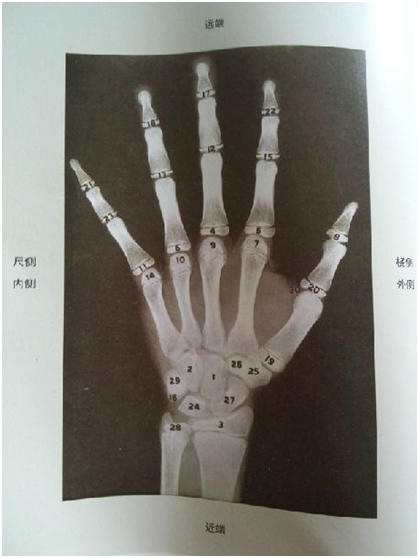

评判孩子的生长空间,不看年龄看骨龄,骨龄是骨骼年龄的简称,是判断孩子长高潜力的重要指标。通过骨龄评估孩子的生长发育水平和成熟程度是更科学的。

假设有两个10岁女孩,身高都是139cm,第1个女孩骨龄已经达到12岁,第2个骨龄只有9岁。那么骨龄9岁的女孩至少还有4年多的生长空间,成年身高应该可以长到165厘米以;而骨龄12岁的女孩,骨龄偏高,生长发育潜力大大减少,所以预估她的成年身高可能只有150cm左右。

所以,年龄年龄相同,身高相同的孩子,他们的终身高可能差异会很大